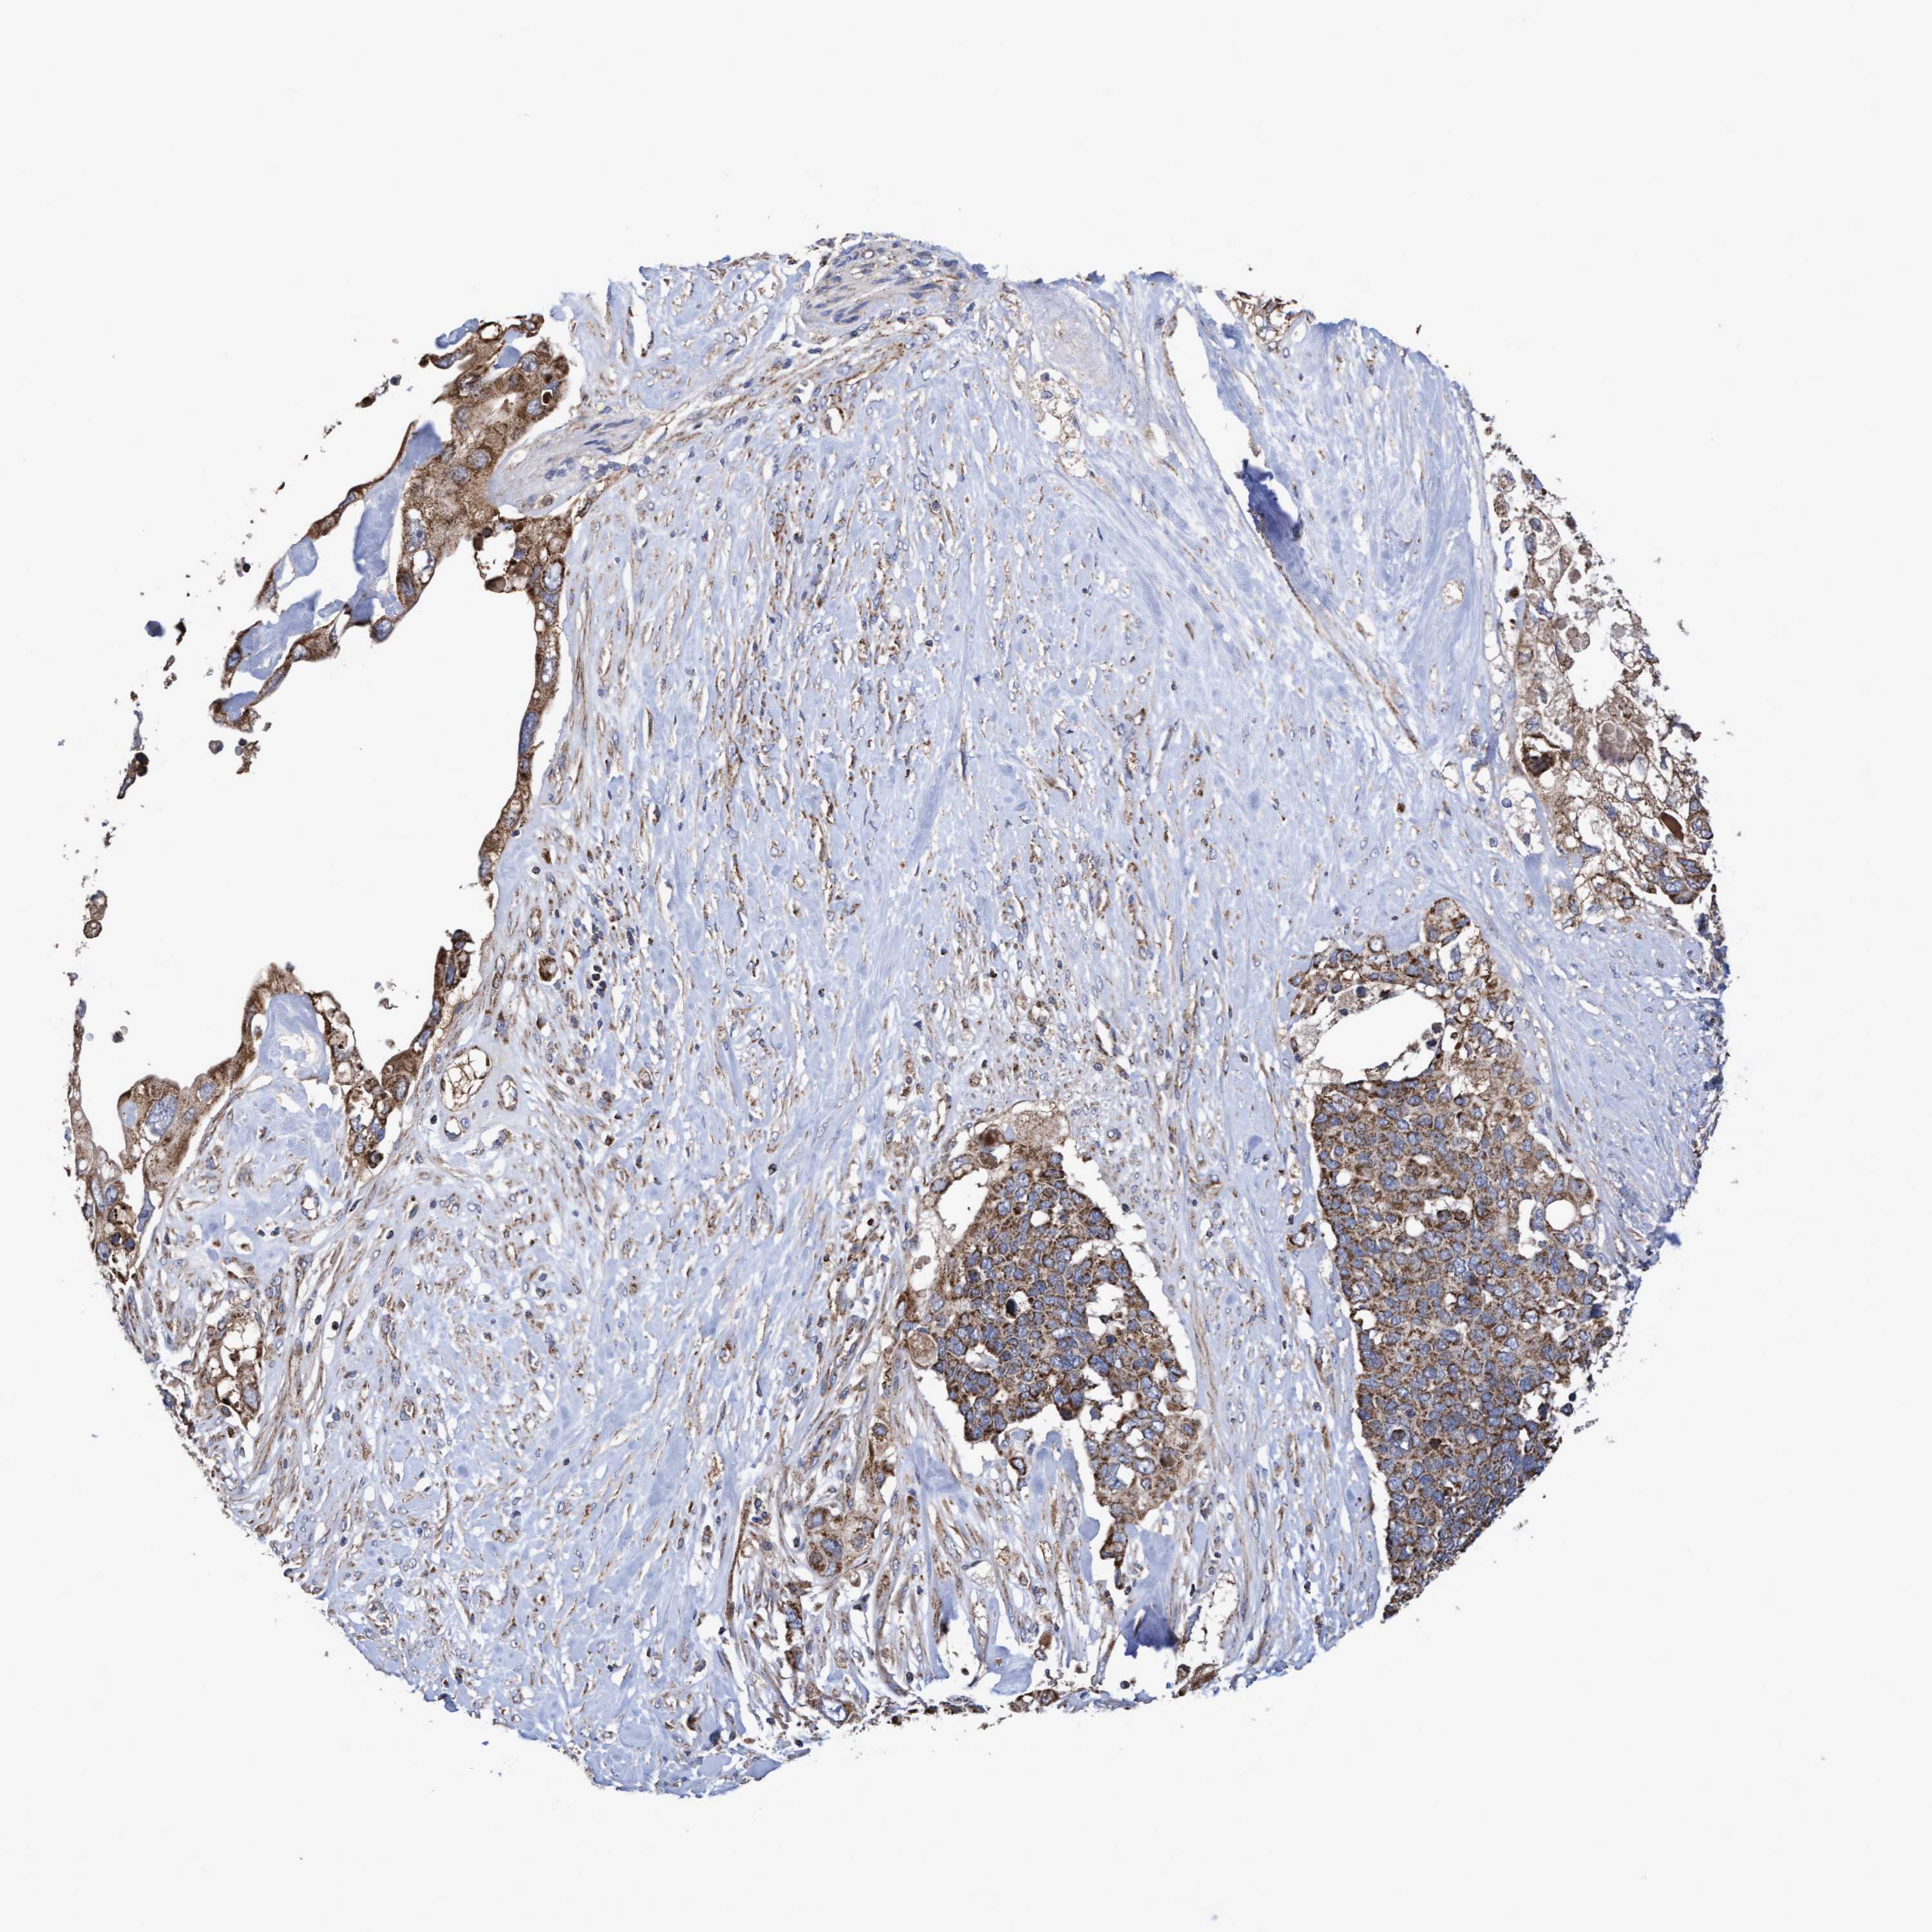

PANCREATIC CANCER - Protein expressioni

A mouse-over function shows sample information and annotation data. Click on an image to view it in a full screen mode. Samples can be filtered based on level of antibody staining by selecting one or several of the following categories: high, medium, low and not detected. The assay and annotation is described here.

Note that samples used for immunohistochemistry by the Human Protein Atlas do not correspond to samples in the TCGA dataset.

Antibody stainingi

Antibody staining in the annotated cell types in the current human tissue is reported as not detected, low, medium, or high, based on conventional immunohistochemistry profiling in selected tissues. This score is based on the combination of the staining intensity and fraction of stained cells.

Each image is clickable and will lead to virtual microscopy that enables deeper exploration of all samples and also displays staining intensity scores, fraction scores and subcellular localization as well as patient and tissue information for each sample.

Antibody HPA019033

Antibody HPA019167

Staining

High

Medium

Low

Not detected

Intensity

Strong

Moderate

Weak

Negative

Quantity

>75%

75%-25%

<25%

None

Location

Nuclear

Cytoplasmic/membranous

Cytoplasmic/membranous,nuclear

Adenocarcinoma, NOS